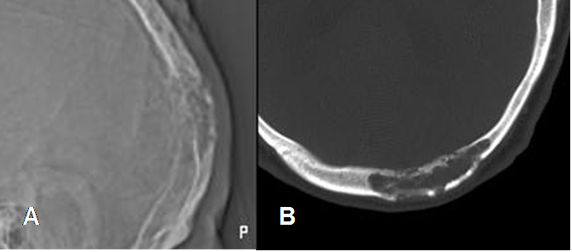

Fig 155. Hemangioma óseo.

A: Rx lateral y B: TAC axial. Lesión permeativa que expande y compromete ambas tablas óseas.

Fig 156. Hemangioma óseo.

A: Rx lateral y B: TAC axial. Lesión radiolúcida y de contornos definidos y no escleróticos.

C: RM axial en T1 y D: RM axial en T2. Esta lesión es hiperintensa en ambas secuencias y corresponde a un hemangioma.